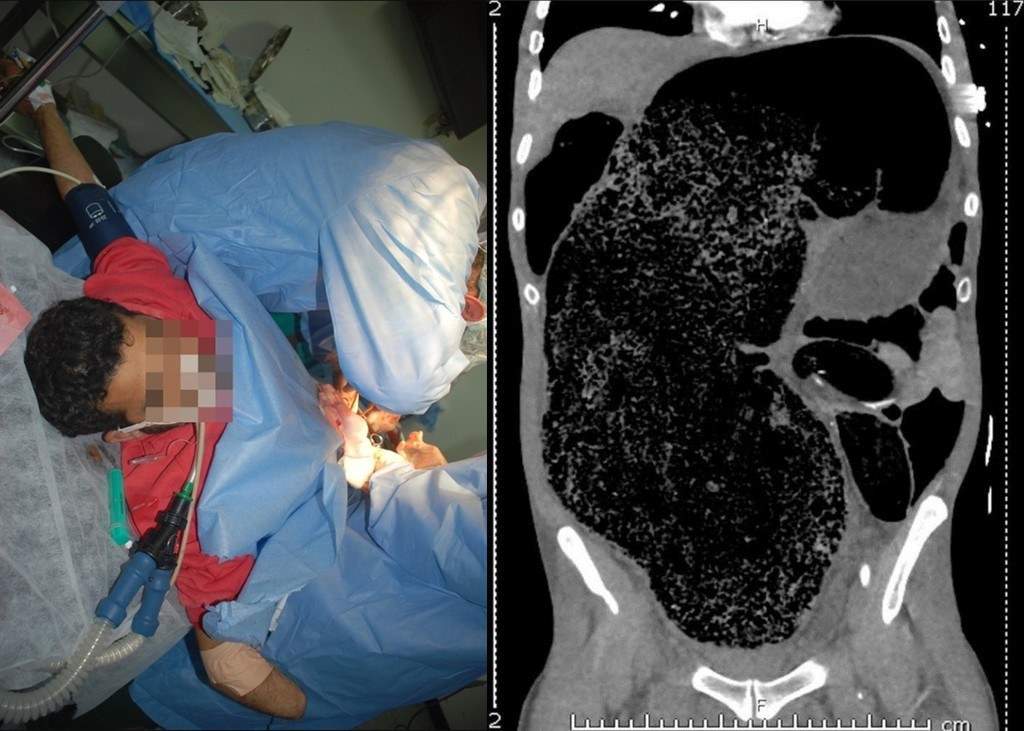

▲屎已經多到壓到其他器官。(圖/翻攝自《太陽報》)

維多利亞州(Victoria)醫生賽門(Simon Ho)在《英國醫學期刊》發表一起離奇案例;這份報告資料顯示,男病患出現胃部疼痛、噁心、便祕、腹脹等情況,右腿甚至已連續麻木24小時,導致無法走動,確診罹患腹部腔室症候群。

醫生聽見病況後趕緊檢查,發現病患四肢手腳冰冷,脈搏也量不太到;而直腸檢驗報告中,他發現病患腹部裡囤積了一大坨糞便,壓迫到下半身的血液循環。醫生表示,病患腎臟嚴重受損與患有代謝性酸中毒,生命已經受到嚴重威脅的緊急狀態,需要立即搶救治療。

醫生賽門醫學團隊立刻幫病患開刀,一共清出2公升的屎,手術相當成功。男病患術後血液循環恢復,右腿麻木感逐漸消失,不過由於患有多器官功能障礙與代謝性酸中毒的關係,得先住進加護病房4天觀察,無大礙後再轉到普通病房做後續觀察,住院第13天後順利出院,右腿也已能靈活使用行走。